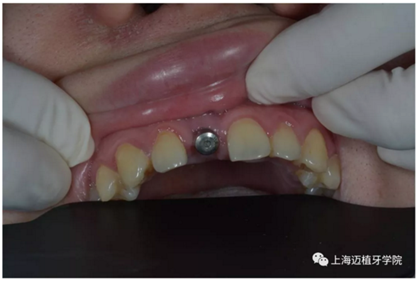

去除愈合基臺(tái):

口內(nèi)個(gè)性化基臺(tái):